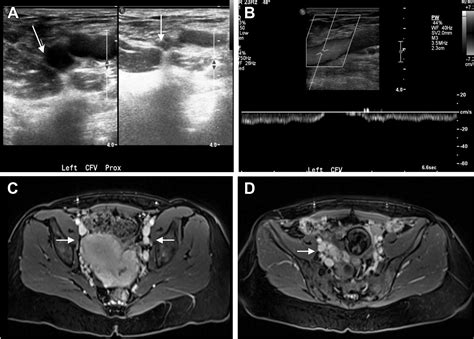

• Doppler ultrasound: To assess blood flow and detect any blockages.

• Venography: A more invasive test that involves injecting a contrast dye into the veins to visualize blood flow.

• CT scan or MRI: To provide detailed images of the veins and surrounding structures.